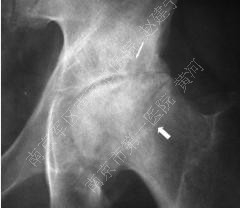

2.影像学检查: 髋部正位片及蛙式位片仍是重要的诊断手段,正位片最初的阳性表现为头下的硬化带及囊性改变,由于正位片中髋臼前后缘与股骨头上方存在重叠,有可能导致病损区显示不清,因此蛙式位片不可或缺,随着病情发展,软骨下骨与软骨分层,X片上则表现为新月征的特点;由于疾病早期X片可无阳性表现,MRI是目前诊断ONFH的“金标准”,其特征性体现在T1加权像上的低密度信号以及T2加权像的高密度信号,是坏死骨与活性骨的交界处出现大量富含血管的肉芽组织的表现。

病损周围环绕硬化带(白箭头)软骨下骨折(黑箭头)以及关节间隙狭窄(细长白箭头)

股骨头坏死进展性变化:病损周围硬化带

(白箭头),关节面塌陷,关节间隙严重狭窄,

髋臼软骨下囊肿形成(细箭头)